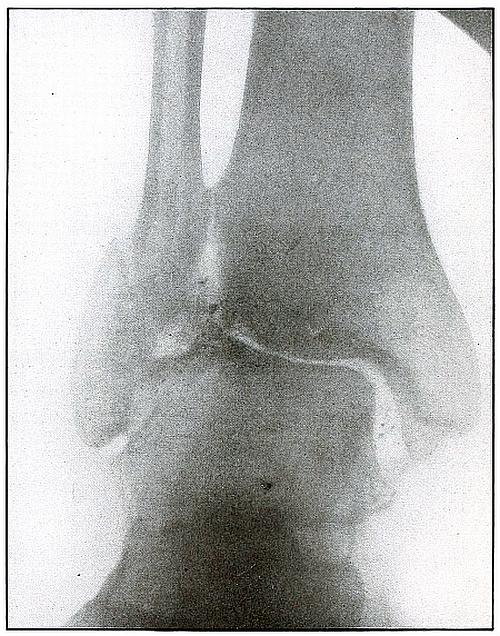

Gunshot fracture, ankle |

154 |